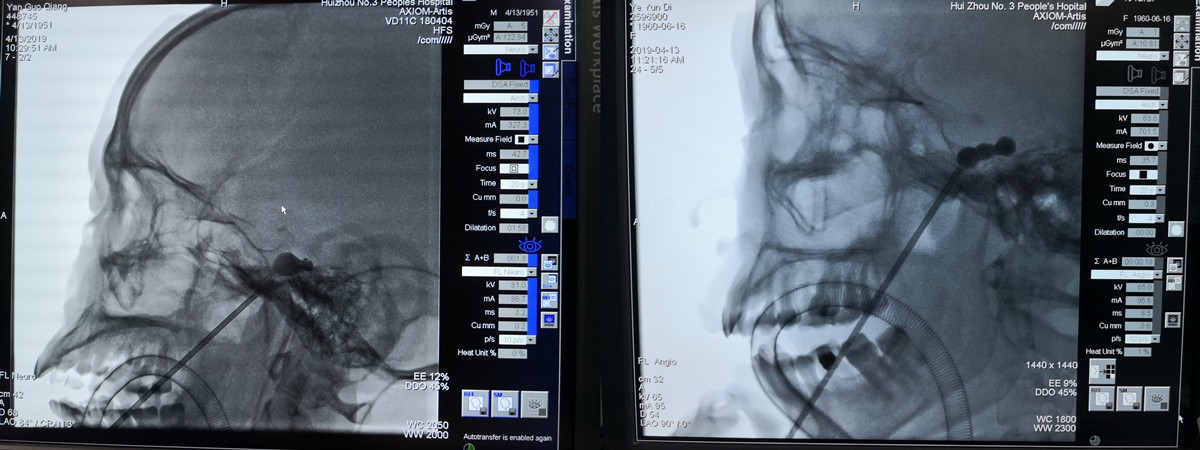

術(shù)中X光片

在此次手術(shù)中,八名患者均在氣管插管全麻下進(jìn)行,術(shù)畢立刻麻醉復(fù)蘇,意識(shí)清醒。術(shù)后安返普通病房,手術(shù)創(chuàng)口僅一個(gè)針眼,手術(shù)完畢臉上僅見(jiàn)一個(gè)創(chuàng)可貼大小輔料,且術(shù)后第二日均能順利康復(fù)出院!